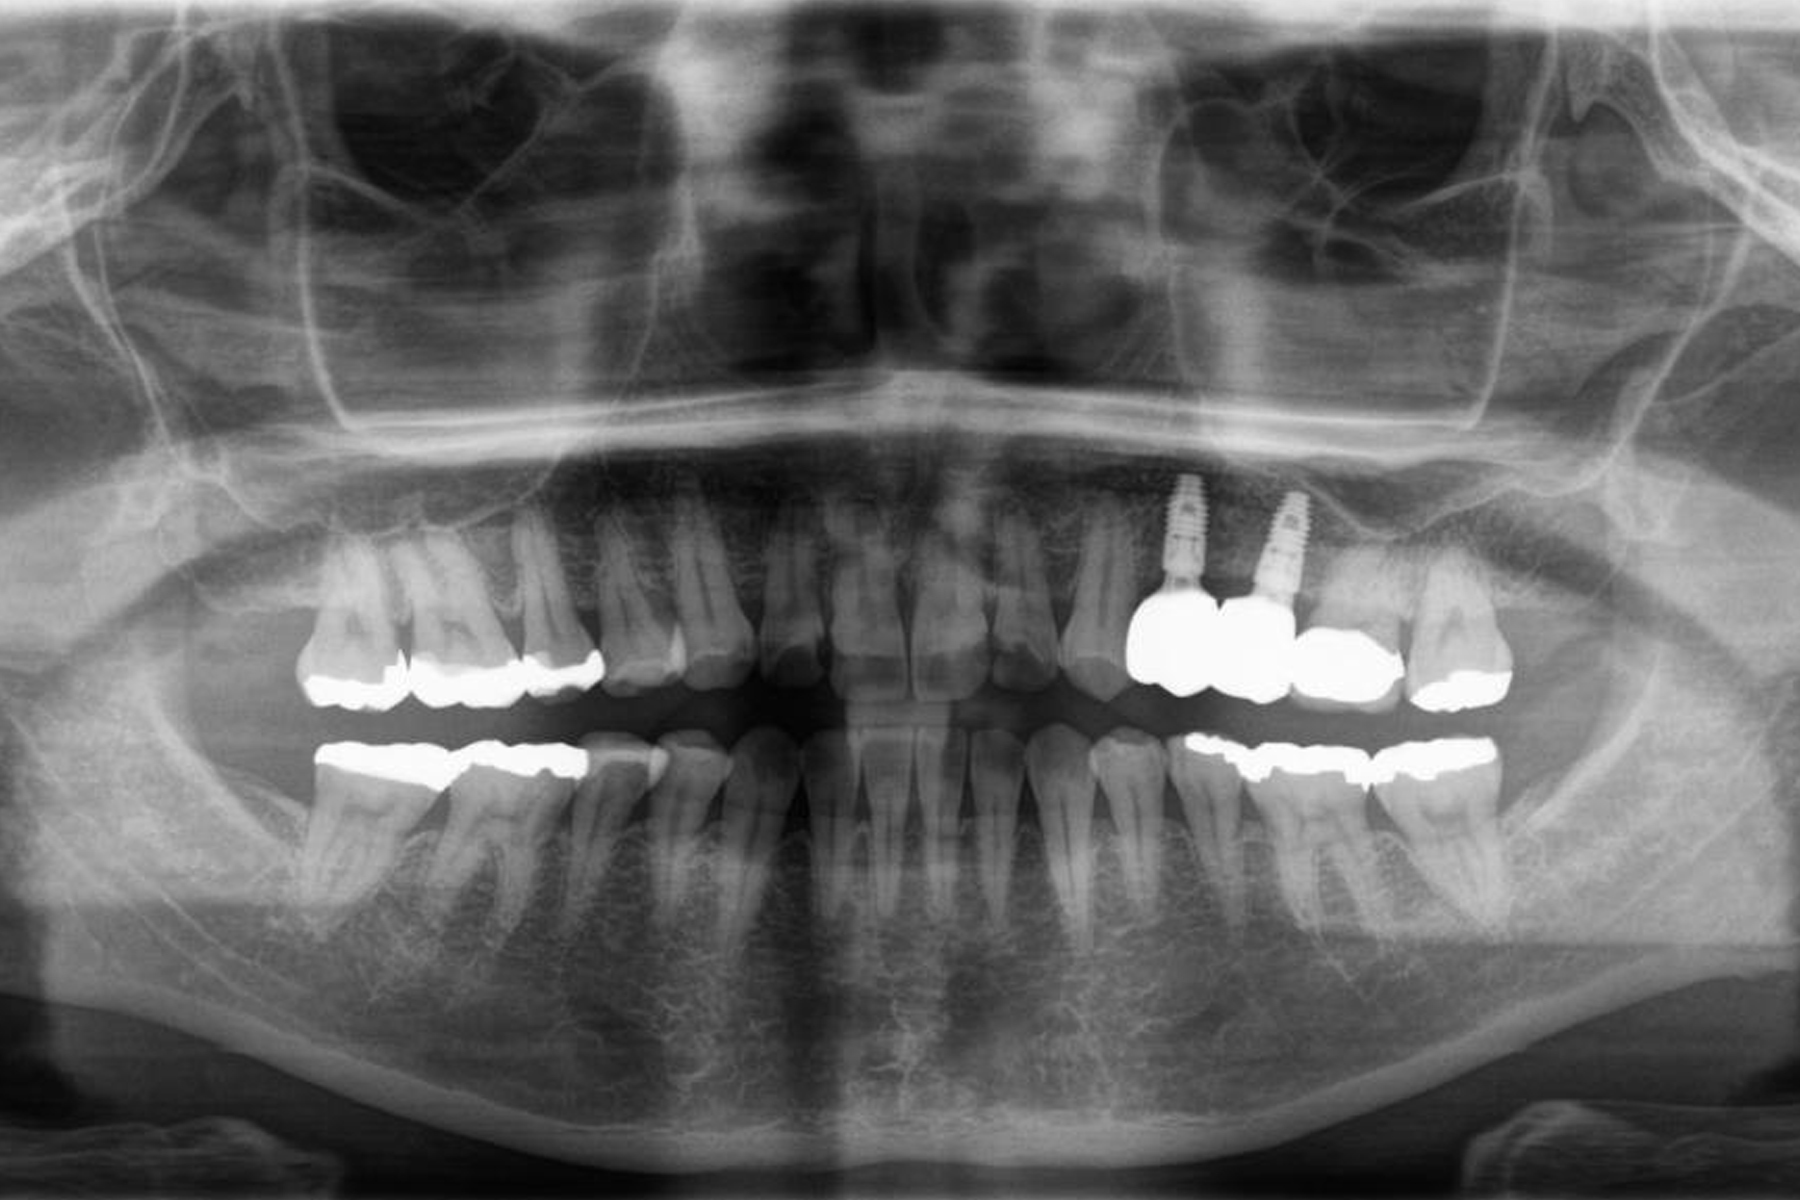

インプラントの症例

Case.1

| 担当医 | 林 大貴 |

|---|---|

| 主訴 | 左上の歯が噛むと痛い |

| 期間 | 約9ヶ月 |

| 治療内容 | 左上4、5番の欠損部位に対して、人工歯根を埋入し上部構造として補綴物をかぶせた。左上4番についてはインプラント埋入の際にソケットリフトを行った。 |

| 治療に伴うリスク | インプラントは、過剰な咬合力がかかった場合、インプラント周囲炎により骨の吸収を認めることがある。 インプラント周囲炎の可能性があるためメンテナンスが必要。 |